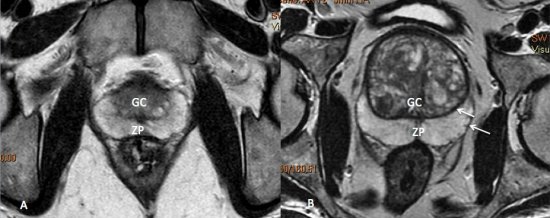

Os achados que indicam invasão das vesículas seminais incluem: aumento de tamanho, assimetria e hipointensidade das vesículas seminais, obliteração do ângulo vesicoprostático e extensão direta da base prostática à vesícula seminal, sendo este achado o de maior valor preditivo positivo.15,18 (fig. 5 e 6).

Figura 5. Estadiamento de adenocarcinoma de próstata Gleason 7. Imagem ponderada em T2 evidencia nódulo no terço médio da zona periférica direita, notando-se pequena irregularidade da cápsula prostática adjacente à lesão, sugestivo de extensão extra-prostática.

Figura 6. Estadiamento de adenocarcinoma da próstata Gleason 9. A) Lesão hipointensa comprometendo quase toda a glândula, com extensão para a gordura periprostática à direita. B) Comprometimento das vesículas seminais.